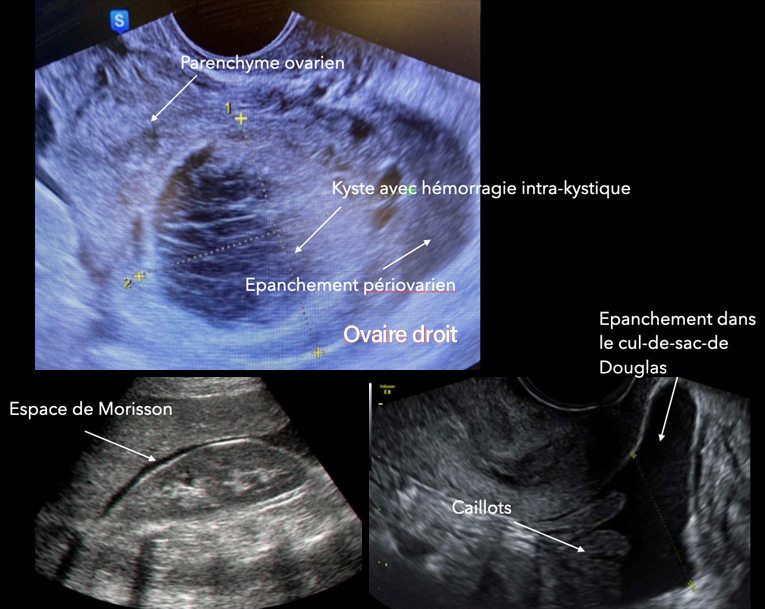

L’échographie pelvienne est la suivante (fig. 4).

Figure 4 (Rodolphe Matias de Sousa, La Revue du Praticien)

Cliniquement, l’hypotension, la tachycardie et les vertiges doivent faire évoquer un saignement actif. À l’échographie, il y a en effet un épanchement abondant dans le cul-de-sac de Douglas remontant jusqu’à l’espace de Morrison.

La douleur brutale post-rapport sexuel, l’instabilité hémodynamique, l’aspect d’hémorragie intra-kystique avec cet aspect hétérogène « en toile d’araignée » du kyste et l’hémopéritoine doivent faire évoquer une rupture hémorragique du kyste.

L’instabilité hémodynamique et le caractère probablement encore actif du saignement impose une cœlioscopie exploratrice en urgence.